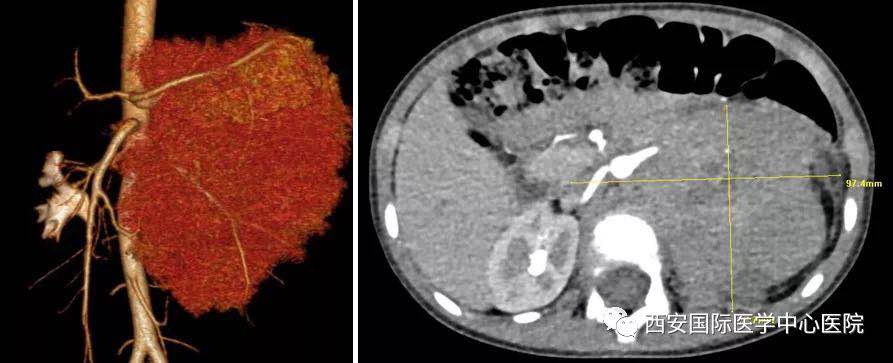

入院后,楊增悅主任仔細(xì)詢問病史、查閱影像學(xué)資料,第一時(shí)間為依依安排骨髓穿刺活檢,最終確診為:腹膜后神經(jīng)母細(xì)胞瘤(Ⅳ期/L2)。CT顯示腫瘤巨大,侵及腹主動(dòng)脈、腹腔干、腸系膜上動(dòng)脈、雙腎動(dòng)脈、腸系膜下動(dòng)脈、下腔靜脈、雙腎靜脈、左腎及腎上腺、胰十二指腸、脾臟、結(jié)腸脾曲;腹膜后多發(fā)淋巴結(jié)轉(zhuǎn)移、骨轉(zhuǎn)移。骨穿病檢示:神經(jīng)母細(xì)胞瘤骨髓轉(zhuǎn)移,腫瘤細(xì)胞占90.5%。經(jīng)過科室團(tuán)隊(duì)討論后決定,先行新輔助化療后再進(jìn)行手術(shù)治療。